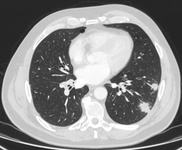

Computed tomography (CT) sections from two cases with benign perifissural nodules. Note the smooth margins and the normal undisturbed adjacent fissure

From the collection of Dr George Tsaknis, MD, PhD, FRCP(London), MRQA, MAcadMEd, PGCert; used with permission